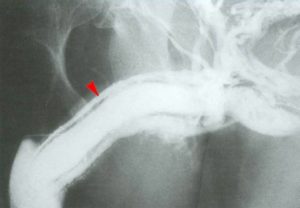

После этого мужчина направляется на ультразвуковое исследование для определения степени кривизны или наличия фиброзной бляшки.

При помощи введенного в член препарата для эрекции и специального транспортира измеряется угол кривизны.